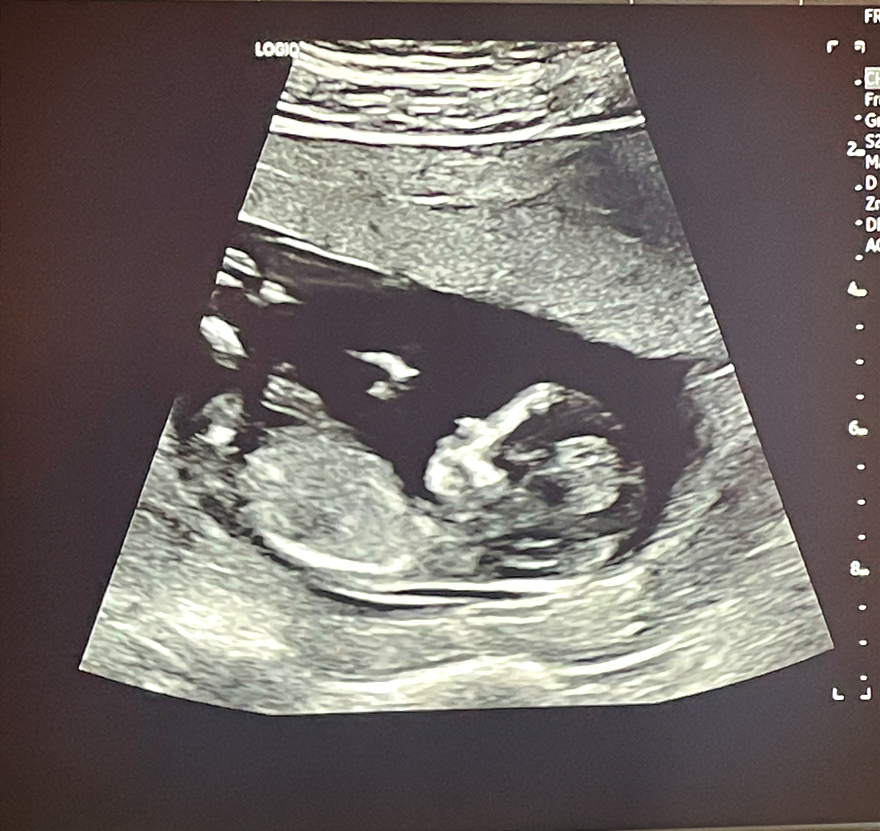

지독했던 입덧이 드디어 끝났다. 16주의 기적.

[입덧 16주 차]

드디어 입덧약을 끊었다. 이젠 좀 살만하긴 한데 무기력하다. 아무것도 하기 싫다. 내 예전의 일상이 어땠는지 기억이 잘 안 난다. 기력이 달린다. 마치 노인이 된 기분이다. 임신 중기가 되면 날아다닌다던데 나는 무기력하고 기운이 없다.

이렇게 지긋지긋했던 입덧 기간이 드디어 지났고 이제야 노트북을 열고 글을 쓸 수 있게 되었다. 임신하면 그 기간에 느꼈던 감정을 글로 남기고 싶은 야심 찬 계획이 있었는데 16주가 지난 지금에서야 겨우 글을 쓰고 있다.